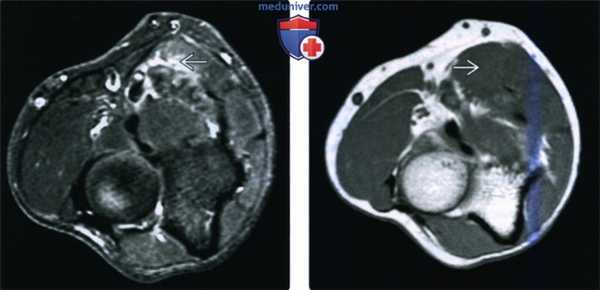

(Слева) На осевой MPT Т2ВИ FS проксимальной трети предплечья определяется незначительное повышение сигнала, указывающее на отек в круглом пронаторе, симптом в результате импиджмента срединного нерва. У пациента две недели назад произошел перелом средней трети диафиза плечевой кости.

(Справа) На осевой MPT Т1ВИ у этого же пациента атрофия круглого пронатора не определяется, так как импиджмент срединного нерва развился относительно недавно. Очевидно, что скоро произойдет жировое замещение мышечных волокон.

(Слева) На осевой MPT Т2ВИ FS дистальной трети предплечья можно видеть денервацию квадратного пронатора и часть глубокого сгибателя пальцев.

(Справа) На осевой MPT PDBИ FS у другого пациента определяется усиление сигнала от круглого пронатора в результате ранней денервации. На момент исследования атрофия отсутствует.